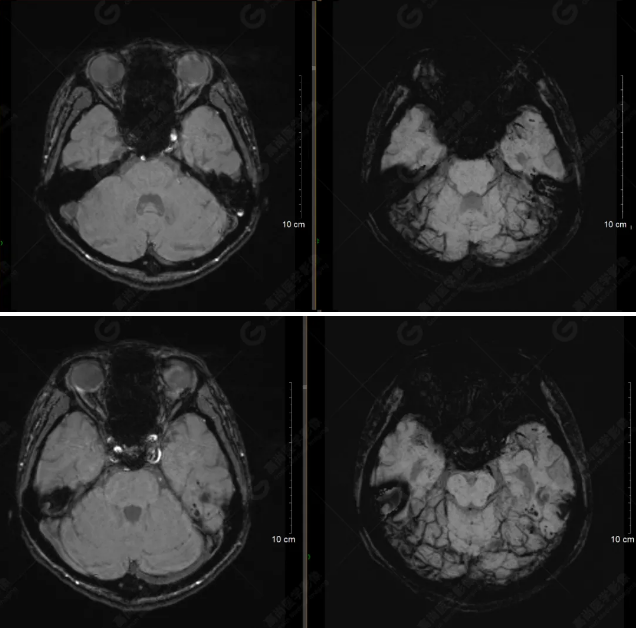

(左側(cè)為薄層原始圖像,右側(cè)為后處理5mm圖像)

SWI序列影像表現(xiàn)及診斷

左側(cè)額底及左側(cè)顳葉內(nèi)見多發(fā)斑點狀極低信號影??紤]額顳葉多發(fā)腦挫傷伴微出血、含鐵血黃素沉著,左側(cè)乳突骨折、乳突內(nèi)積血。討論:1、SWI利用不同組織間磁敏感的差異成像并將其放大,通過檢測病灶中的靜脈分布、出血灶和礦物質(zhì)沉積等,有效改善了相關(guān)疾病的診斷,主要應(yīng)用于中樞神經(jīng)系統(tǒng)。2、根據(jù)磁距圖像和相位圖像表現(xiàn),對于鑒別顱內(nèi)出血及鈣化有一定程度的價值,用于彌補(bǔ)MRI對鈣化顯示的不足。

磁敏感加權(quán)成像(SWI) 以T2*加權(quán)梯度回波序列作為序列基礎(chǔ),根據(jù)不同組織間的磁敏感性差異提供圖像對比增強(qiáng),可同時獲得磁距圖像和相位圖像。該技術(shù)早期主要應(yīng)用于腦內(nèi)小靜脈的顯示,近年來經(jīng)過高場磁共振儀的應(yīng)用及相關(guān)技術(shù)的不斷改進(jìn),其臨床應(yīng)用范圍得到了極大的擴(kuò)展。SWI能夠比常規(guī)梯度回波序列更敏感地顯示出血,甚至是微小出血,在診斷腦外傷、腦腫瘤、腦血管畸形、腦血管病及某些神經(jīng)變性病等方面具有較高的價值及應(yīng)用前景。